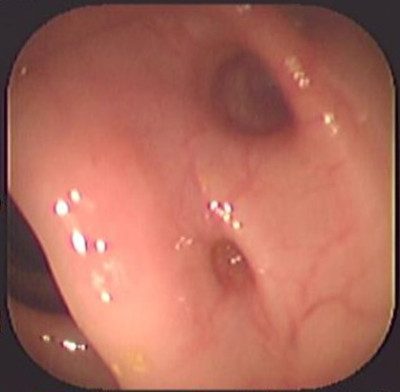

Enfermedad diverticular del colon

Envíado por Dr. Carlos Ernesto Arévalo